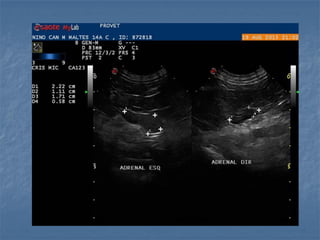

Hiperplasia adrenal bilateral

 Hiperadrenocorticismo  Hipofisáriodependente: há um aumento bilateral (80% dos casos!), pode ser simétrico ou assimétrico * Medida normal de espessura menor que 0,74cm cães adultos